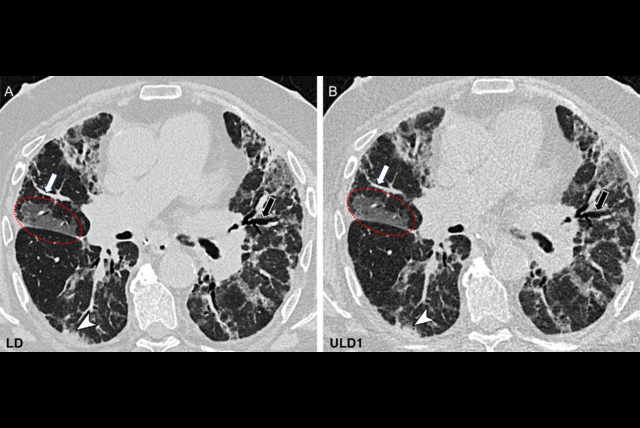

Wradzidlo and colleagues compared image quality and radiation dose between a dual-energy CT (DECT) device and a photon-counting CT scanner. Their study included 70 patients who underwent abdominal, contrast-enhanced CT between November 2021 and February 2022. The patients had both a DECT exam and a follow-up exam with a photon-counting device (median time between the two scans was four months). The researchers assessed radiation dose between the two types of studies using the following metrics: CT dose index, dose length product, and size-specific dose estimation. Two radiologists scored the images for quality, particularly lesion visibility.

Additionally, the two readers rated lesion conspicuity higher on the photon-counting CT exams compared with the DECT exams, especially in the third quartile, the team noted.